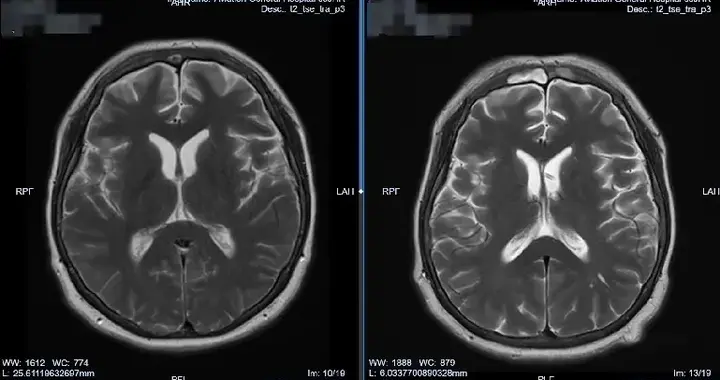

10月大患儿脑积水微创治愈,软性神经内镜技术立大功